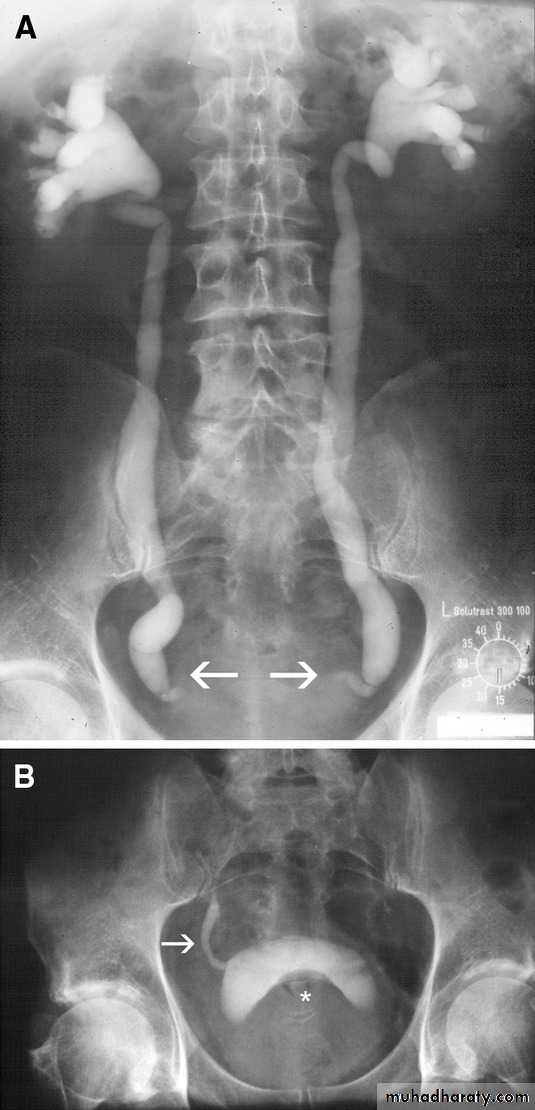

PROSTATIC Enlargement

Common cause of lower urinary obstruction . Either Benign prostatic hyperplasia or Carcinoma .Benign Hyperplasia :-

• IVU ( cystogram stage )

• * Elevated bladder base .• *Lower ureter elevated and curved (fish hook ).

• * Back pressure to both kidney & ureters .

• * Thick trabeculated bladder wall and diverticula formation .

• * Large size prostate produce filling defect like appearance .

• * Post-voiding residual volume .